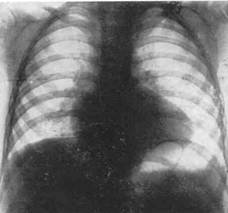

Дівчинка 11 міс. Cкарги батьків на швидку її втомлюваність при годуванні, раптове посилення ціанозу та задухи при плачі. Об¢єктивно: Стан середньої важкості, відставання в фізичному розвитку. В спокої – помірно виражений ціаноз шкірних покривів, слизові з фіолетовим відтінком, ціаноз посилюється при плачі дитини. Під час огляду на фоні неспокою значно посилився ціаноз, почастішало дихання, дитина стала вкрай неспокійною, на руках у матері з притиснутими до живота ніжками трохи заспокоїлась. Дихання 64 на хв, над легенями ясний перкуторний звук, жорстке дихання Пульс 150 за хв. Межі серця: розширені вправо. Над всією поверхнею грудної клітки вислуховується грубий систолічний шум із максимальною звучністю в 2-му міжребер'ї зліва від грудини, другий тон ослаблений над легеневою артерією. Загальний аналіз крові: Hb -200 г/л; еритроцити – 6,0 Т/л, КП – 0,95; нейтрофіли: паличкоядерні -5%, сегментоядерні -39%; еозинофіли-3%; лімфоцити-50%; моноцити - 3%; ШЗЕ - 4 мм/год. Рентгенологічне обстеження ОГК: див. рис.

Дівчинка 11 міс. Cкарги батьків на швидку її втомлюваність при годуванні, раптове посилення ціанозу та задухи при плачі. Об¢єктивно: Стан середньої важкості, відставання в фізичному розвитку. В спокої – помірно виражений ціаноз шкірних покривів, слизові з фіолетовим відтінком, ціаноз посилюється при плачі дитини. Під час огляду на фоні неспокою значно посилився ціаноз, почастішало дихання, дитина стала вкрай неспокійною, на руках у матері з притиснутими до живота ніжками трохи заспокоїлась. Дихання 64 на хв, над легенями ясний перкуторний звук, жорстке дихання Пульс 150 за хв. Межі серця: розширені вправо. Над всією поверхнею грудної клітки вислуховується грубий систолічний шум із максимальною звучністю в 2-му міжребер'ї зліва від грудини, другий тон ослаблений над легеневою артерією. Загальний аналіз крові: Hb -200 г/л; еритроцити – 6,0 Т/л, КП – 0,95; нейтрофіли: паличкоядерні -5%, сегментоядерні -39%; еозинофіли-3%; лімфоцити-50%; моноцити - 3%; ШЗЕ - 4 мм/год. Рентгенологічне обстеження ОГК: див. рис.

1. Який попередній діагноз? Яке ускладнення розвинулось у дитини? Опишіть патологічні зміни в аналізі крові, на ЕКГ, ЕхоКГ та на рентгенограмі.